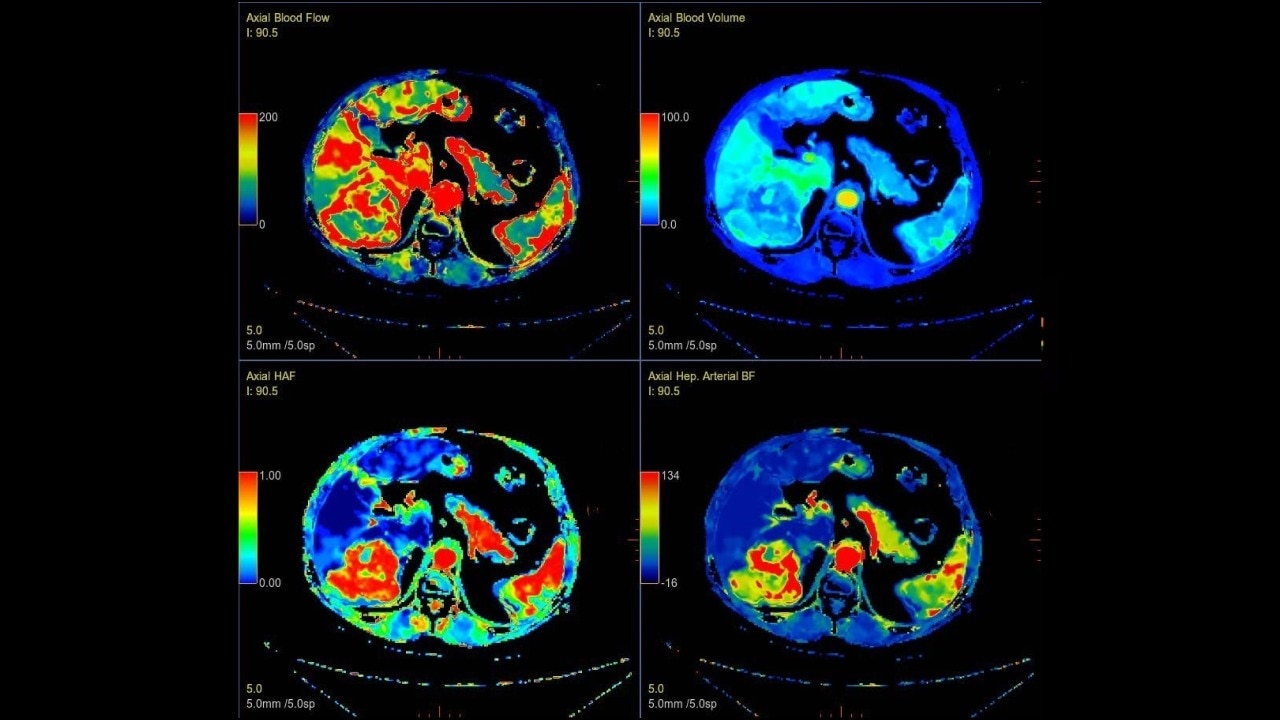

Body perfusion

Optimized protocols for kidney, soft tissue, liver perfusion and other body tumors